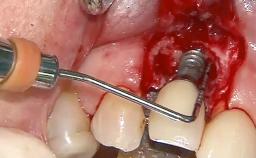

Surgical Management of Peri-Implantitis: Reconstructive Surgical Treatment with Three-Year Follow-up After Treatment

Despite anti-infective surgical treatment, some patients may experience recurrent infection and progressive bone loss requiring additional treatment. Removal of Implant Due to Recurrent Infection describes a conservative approach using an implant retrieval tool without the need for excessive bone removal or use of a trephine.